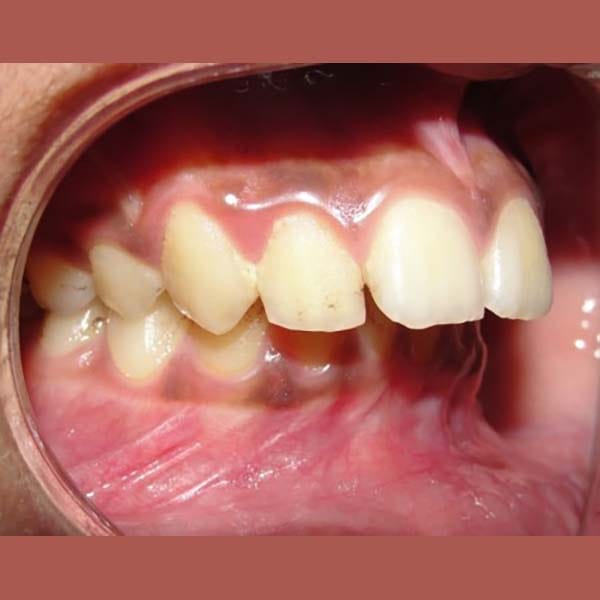

عانى هذا الشاب اليافع من بروز شديد في الأسنان وصل إلى 1 سم، وكان سببه الرئيسي هو تراجع الفك السفلي، وهو ما كان يظهر بوضوح على بروفيل وجهه الجانبي.

تم العلاج على مرحلتين لاستغلال فترة النمو:

كما تظهر الصور، كان التحسن جذرياً ليس فقط في الابتسامة ولكن في تناسق ملامح الوجه بالكامل. تم تصحيح البروز، وتحسنت علاقة الفكين، وحصل الشاب على ابتسامة جميلة وواثقة.